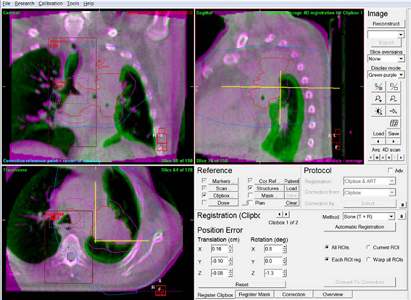

IGRT

IGRTとは、照射の直前や照射中にX線写真やCT画像を取得して、治療計画時の画像と重ね合わせて、骨やマーカーなどをもとに正確に合わせ込みを行い、位置のずれの量を求めて寝台位置の修正を行ってから照射を行います。